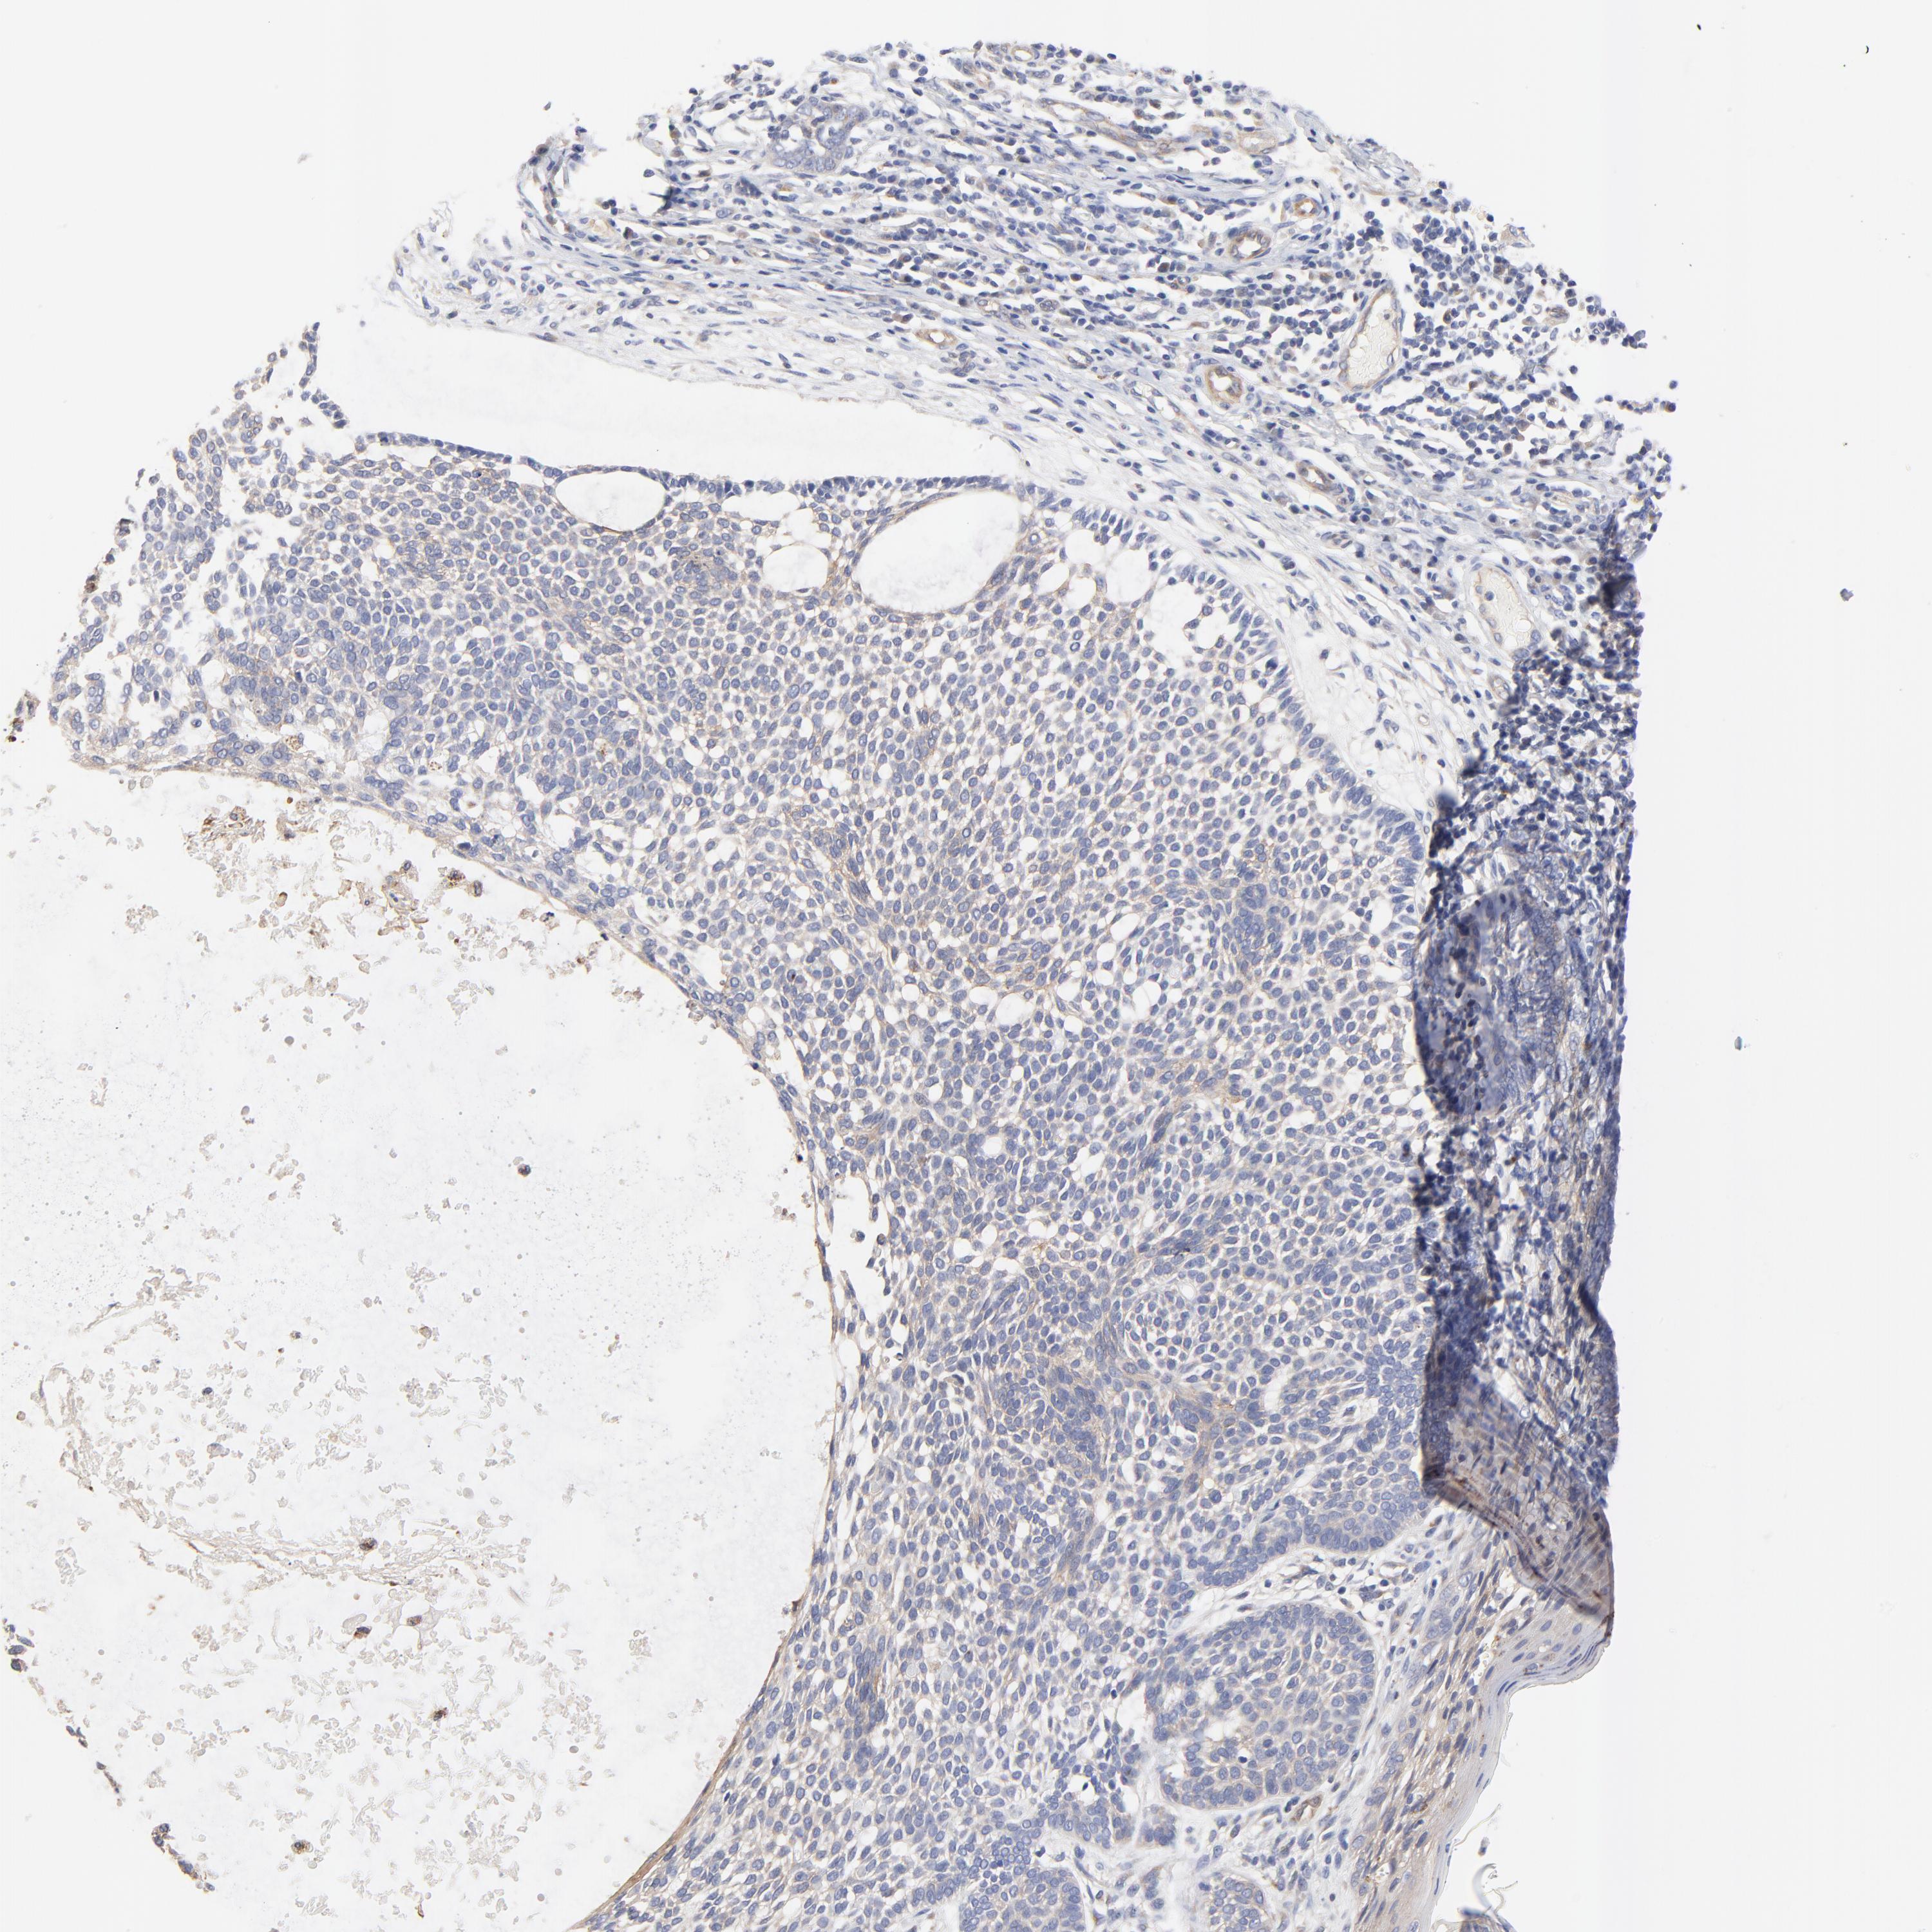

SKIN CANCER - Protein expressioni

A mouse-over function shows sample information and annotation data. Click on an image to view it in a full screen mode. Samples can be filtered based on level of antibody staining by selecting one or several of the following categories: high, medium, low and not detected. The assay and annotation is described here.

Each image is clickable and will lead to virtual microscopy that enables deeper exploration of all samples and also displays staining intensity scores, fraction scores and subcellular localization as well as patient and tissue information for each sample.

Antibody HPA003240

Basal cell carcinoma